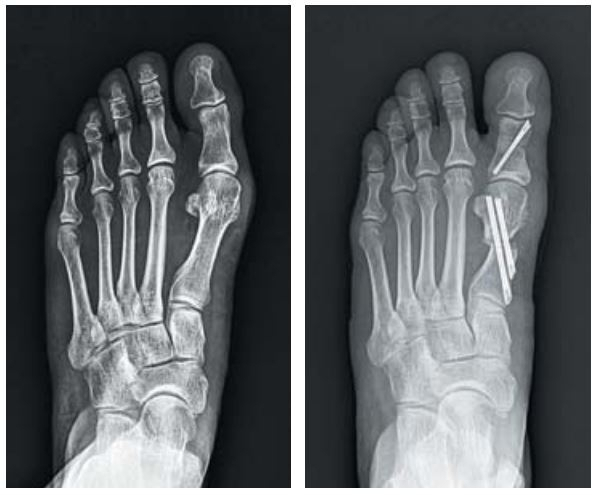

작은 사진은 무지외반증 수술전(왼쪽)과 후 엑스레이 영상자료. 구포성심병원 제공